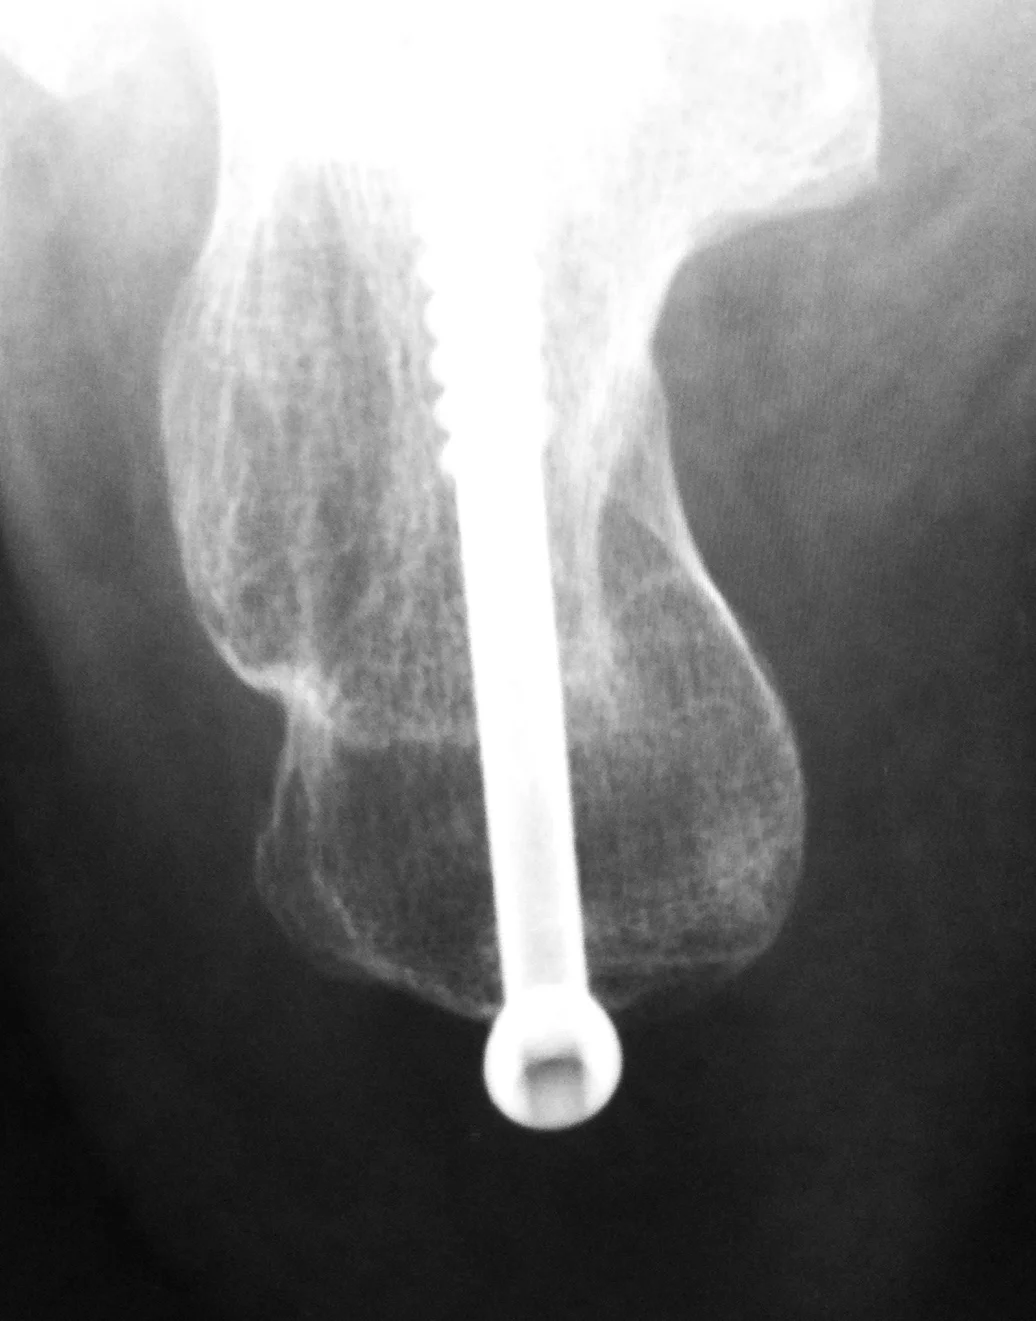

Mr Redfern performs this surgery through two 1cm incisions which are literally a fraction of the size used with open surgery. Using these small incisions, he can re-align the heel bone using a tiny drill (burr) to cut the calcaneum, re-align it and then fix it in position using a screw. This is all carried out using high-tech image guidance (x-ray image intensifier).

Here is an MRI of a minimally invasive calcaneal osteotomy that has healed. The scan image has been annotated to show the site of the cut and the direction of re-alignment. The position of the important tibial nerve and blood vessels has also been marked to show that they are well clear of the site of the keyhole surgery. The risk of kind of nerve injury is less than 1:500 in Mr Redfern’s practice.